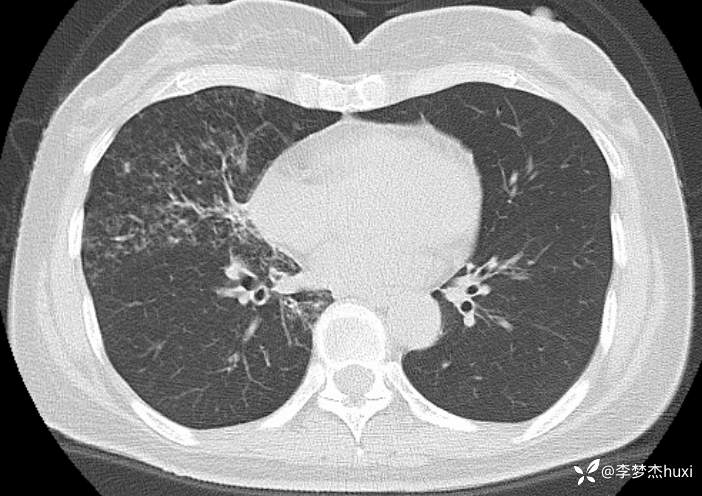

女性53岁,腮腺癌术后反复咳嗽、咳痰,胸部CT以树芽征为特点改变,最可能的是哪种疾病

2.既往高血压病史20余年,最高达180/?mmHg,目前口服“缬沙坦胶囊、硝苯地平控释片、酒石酸美托洛尔”等药物治疗,血压未监测;2008年因右侧腮腺腺样囊性癌于天津肿瘤医院行手术治疗,术后给予放化疗,2019年肿瘤原位复发,于北京大学口腔医院再次行手术治疗,2023-8发现肿瘤侵犯右耳道,目前口服仑伐替尼治疗约12个月;2023-11开始应用帕博利珠单抗注射液免疫治疗,患者右肺上叶占位,2024-7于沧州市中心医院行穿刺活检,病理:腺样囊性癌,2024-08于北京市某医院行“肺部射频消融术”;患者术后时常呛咳,否认“冠心病、糖尿病”病史,否认“肝炎”、“结核”等传染病史;否认外伤史,无输血史;否认食物、药物过敏史,预防接种史不详,系统回顾无特殊。。

【临床诊断】: 1.肺炎

2.肺恶性肿瘤 (腺样囊性癌)射频消融术后。

【治疗经过及结果】:抗感染治疗

考虑哪种疾病可能大?